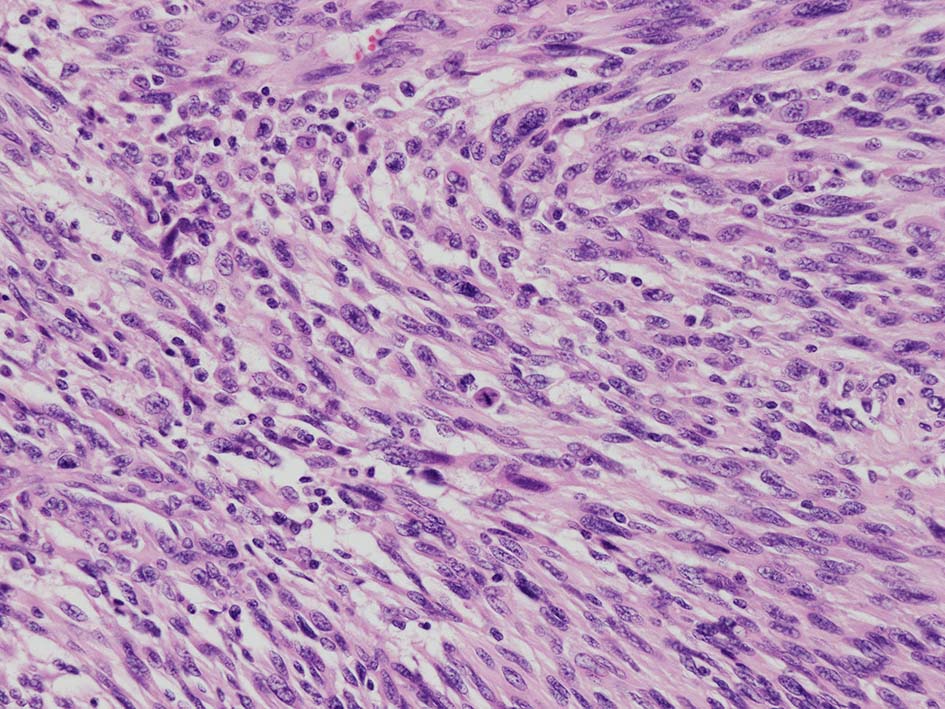

紡錘形異型メラノサイトが著明な間質反応(desmoplasia)を伴い増殖する特殊な色素性病変。*1. desmoplastic neurotropic melanomaは, desmoplastic melanomaのうち神経向性(neurotropism:神経周囲侵襲像)がめだつものでReedら*2が最初に報告した。

いずれも腫瘍細胞の異型性が乏しく, 背景の間質反応がめだつこと, メラニンの存在が目立たないことが特徴である。

病理組織所見*4

リンパ濾胞が細血管周囲に形成され, この部分に異型といえる細胞が増加している(S100+)

再発腫瘤病変の組織像